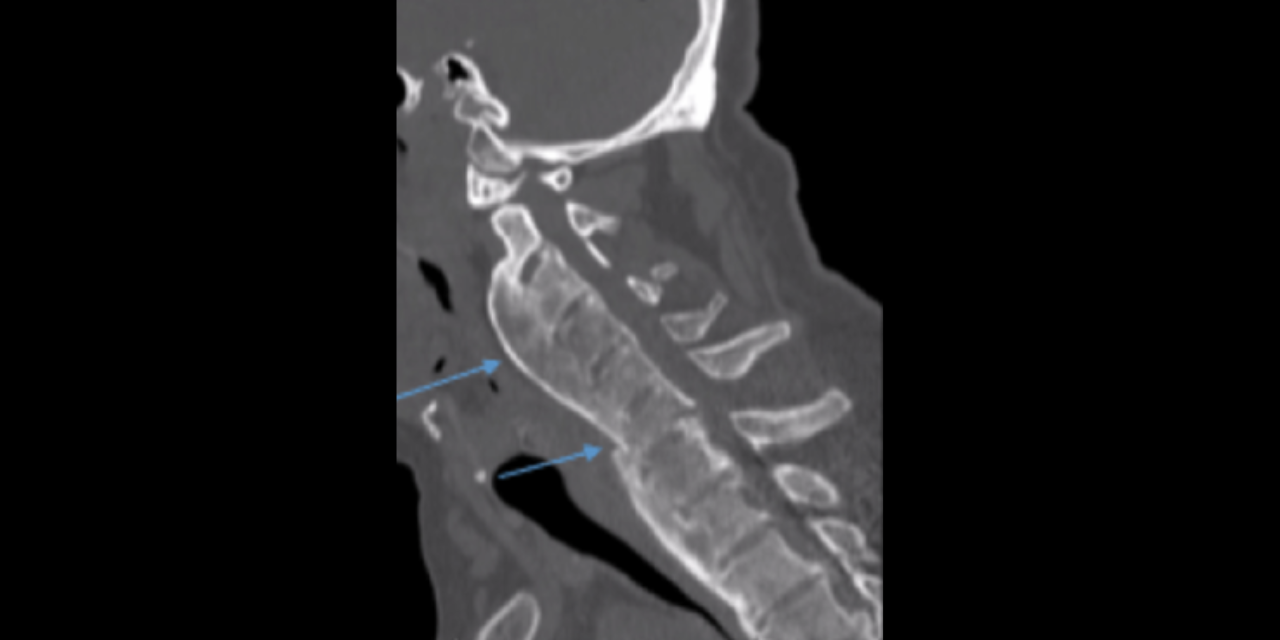

1) Ossification of the posterior longitudinal ligament (OPLL)

OPLL is present in approximately 50% of patients with cervical DISH and is most common in the cervical spine, representing 75% of all OPLL cases (2). OPLL may occur in the thoracic and lumbar spine as well. It is twice as common in men than women and slightly more common in Asian countries (3). Patients with OPLL may be asymptomatic or present with symptoms consistent with central canal stenosism such as radiculopathy and myelopathy. Cord injury from minor trauma is also a greater risk in those patients with OPLL, particularly in the cervical spine. CT imaging is the best imaging modality to assess the degree of central canal stenosis. Treatment may be conservative, but surgical treatment may be appropriate when neurologic symptoms are present. Great care and caution should be taken when assessing and treating your patients with OPLL.

2) Chalk stick fracture

The most important risk fracture of DISH with or without OPLL is the risk of a chalk stick fracture due to ankylosis of the spine. Most all practitioners easily remember the risk of chalk stick (aka carrot stick) fracture in inflammatory spondyloarthropathies such as ankylosing spondylitis, but often fail to recognize DISH as a risk factor for this same type of fracture. A chalk stick fracture is an unstable fracture through ankylosed vertebrae, regardless of the etiology of the ankylosis. These fractures can occur following minor trauma, such a trip on a curb, in conditions such as AS and DISH.